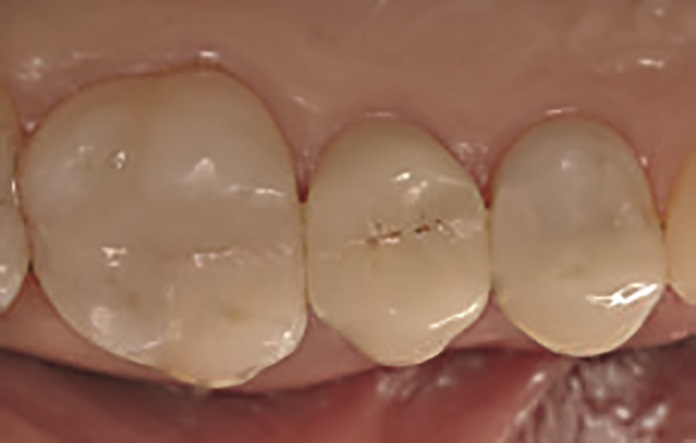

Odbudowę zęba przeprowadzono zgodnie z techniką warstwową. Pierwsza warstwa Harmonize™ w odcieniu siecznym została zaaplikowana w celu odtworzenia ściany interproksymalnej, przekształcając w ten sposób klasę II w klasę I ubytku. Następnie zaaplikowano początkową warstwę w odcieniu zębinowym, a następnie drugą — jaśniejszą i o mniejszym stopniu nasycenia — w odcieniu szkliwnym. Każda z warstw została poddana polimeryzacji przez 20 sekund lampą Demi Ultra, zapewniającą wysokie natężenie światła (1100‑1300 mW/cm²). Po zakończeniu procedury w zębie 16 (ryc. 8), wykonano odbudowę zęba 14. Po umieszczeniu formówki MetaFix (Kerr), charakteryzującej się obecnością wbudowanego napinacza ułatwiającego jej adaptację do powierzchni zęba, przeprowadzono procedurę adhezyjną zgodnie z protokołem selective enamel etching. Na szkliwo zaaplikowano 37,5% kwas ortofosforowy w żelu (Gel Etchant) (ryc. 9), a następnie, po wypłukaniu i wysuszeniu, przeprowadzono analogiczną do opisanej wcześniej w przypadku zęba 16 procedurę z zastosowaniem techniki warstwowej i kompozytu Harmonize™ (ryc. 10). Oba wypełnienia delikatnie skorygowano i wypolerowano za pomocą drobnych, a następnie ultradrobnych diamentów przeznaczonych do opracowania wypełnień kompozytowych (Kerr) (ryc. 11).